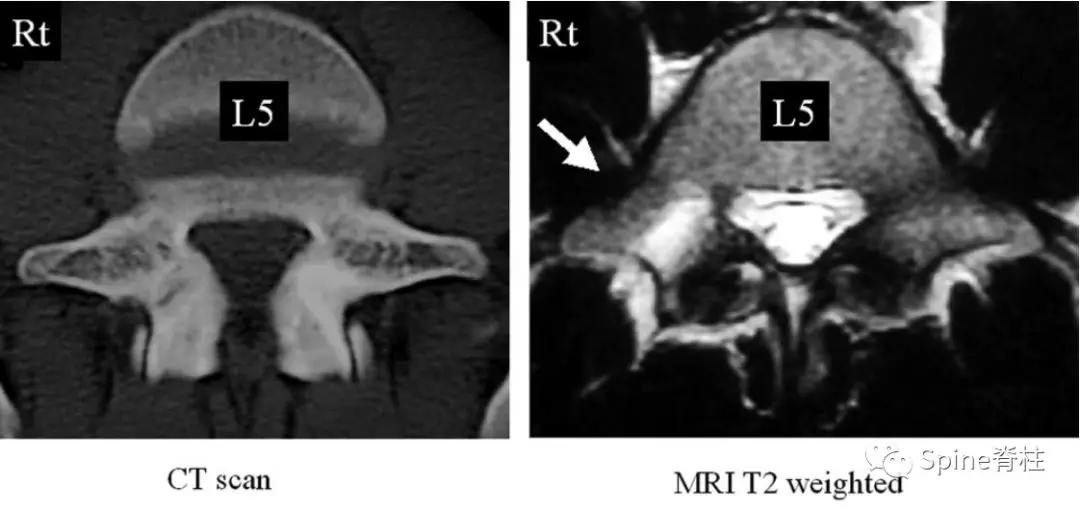

因此, Sairyo教授也提出,对于青少年腰痛患者行MRI检查时,在传统椎间盘层面的基础上(A-C线), 多加一个经椎弓根层面(D线) (影像科医生希望能看到) 。因为,A-C线椎间盘层面可很好看出青少年腰椎间盘突出和腰椎椎体后缘离断症,而D线经椎弓根层面可以早期诊断出腰椎峡部裂和腰椎椎弓根损伤。

- 椎弓根裂 (pediculolysis)是指椎弓根的应力性骨折,常发生在单侧峡部裂的对侧椎弓上。表现为矢壮位MRI的椎弓根呈T1低信号和T2高信号(水肿信号),伴或不伴骨折线。

图:15岁腰痛男孩,左侧腰5椎弓根裂

A:T1左侧腰5椎弓根低信号(箭头);B:T2左侧腰5椎弓根高信号(箭头);C:T2轴位左侧腰5椎弓根骨折线明显,伴高信号区(箭头)。